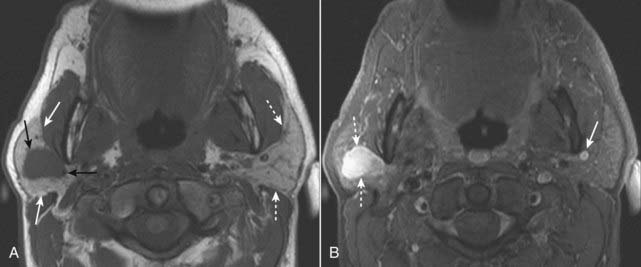

Figure 20-2 Subcapsular hematoma of the kidney.

A, Axial T1-weighted fat-suppressed image demonstrates a bright subcapsular hematoma (solid white arrows) involving the left kidney laterally. We can tell that this is a T1-weighted image because cerebrospinal fluid (CSF) in the spinal canal is dark (open white arrow). B, Axial T2-weighted, fat-suppressed image again demonstrates a slightly bright left subcapsular hematoma with a dark rim of hemosiderin (dotted white arrows) indicating surrounding older blood. There is a small amount of adjacent left perinephric fluid (solid white arrow). The bright signal of the CSF helps us to recognize this image as a T2-weighted image (open white arrow).